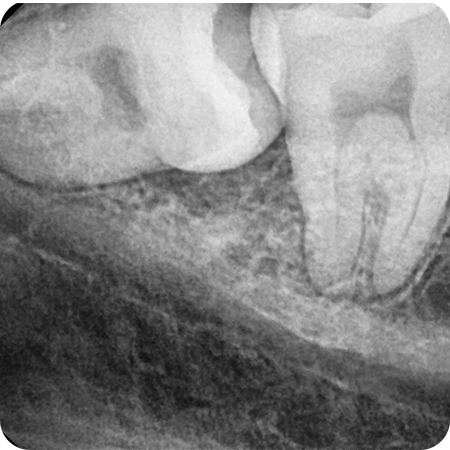

상악 사랑니 발치

상하악 사랑니발치

하악 사랑니 발치

신경관과 같은 해부학적 구조물에 가깝고

매복된 위치와 각도에 따라 잇몸 및 골 삭제 과정이

추가적으로 필요합니다.

전문 장비를 이용해 정확한 진단을 하고

통합치의학과 전문의의 노하우를 바탕으로

안전하게 사랑니 발치를 합니다.